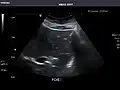

Renal ultrasonography

Ultrasonography of the kidneys is essential in the diagnosis and management of kidney-related diseases. The kidneys are easily examined, and most pathological changes in the kidneys are distinguishable with ultrasound.[7]

Kidneys: Right and left kidneys measure 11.5 cm and 12 cm in length respectively. No hydronephrosis. Small left lower pole kidney cyst.

Right kidney -